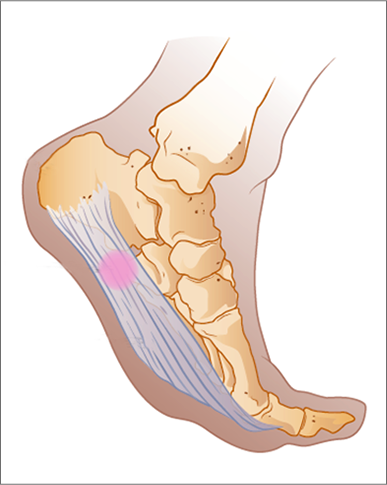

플랜타르 패시아염 (족저근막염)

- 발바닥의 아치에 위치한 두꺼운 섬유 조직인 족저근막이 염증이 생기는 질환입니다. 주로 장시간 서 있거나 걷는 경우, 혹은 비만으로 인해 과도한 압력이 가해져 발생합니다. 통증은 주로 아침에 일어났을 때 첫 발을 내딛을 때 가장 심하게 느껴지며, 점차 운동 후에도 나타날 수 있습니다.